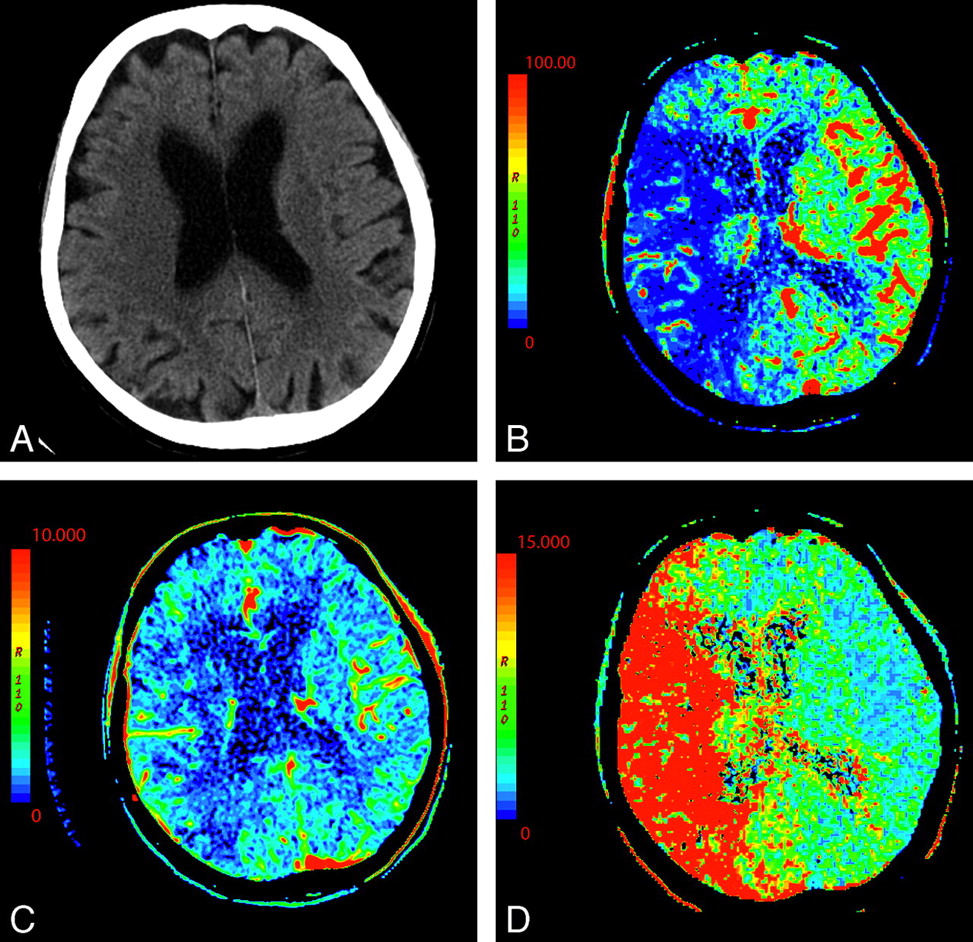

۳. هوا در مجاری صفراوی (Pneumobilia)

یه نشونهی غیرمستقیم اما خیلی مهم، دیدن هوا توی مجاری صفراویه؛ چه داخل کبدی، چه توی CBD. این میتونه یه سرنخ قوی باشه که نشون بده یه راه ارتباطی غیرطبیعی بین کیسه صفرا و روده بهوجود اومده.